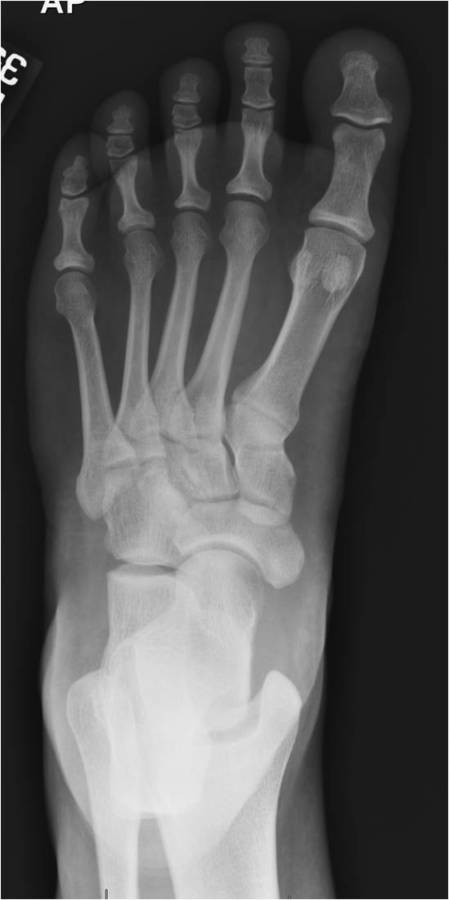

Gallery of Unlabled Radiographs from Lecture (Dr. French) - 2020

Click a thumbnail to enter the gallery display. Click the file name link at the bottom left of the gallery display to view the image at high resolution.